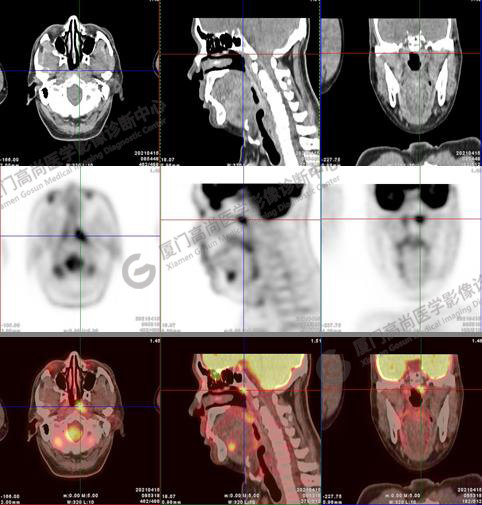

圖6-9:鼻咽左側(cè)壁增厚,代謝異常增高,考慮為鼻咽癌